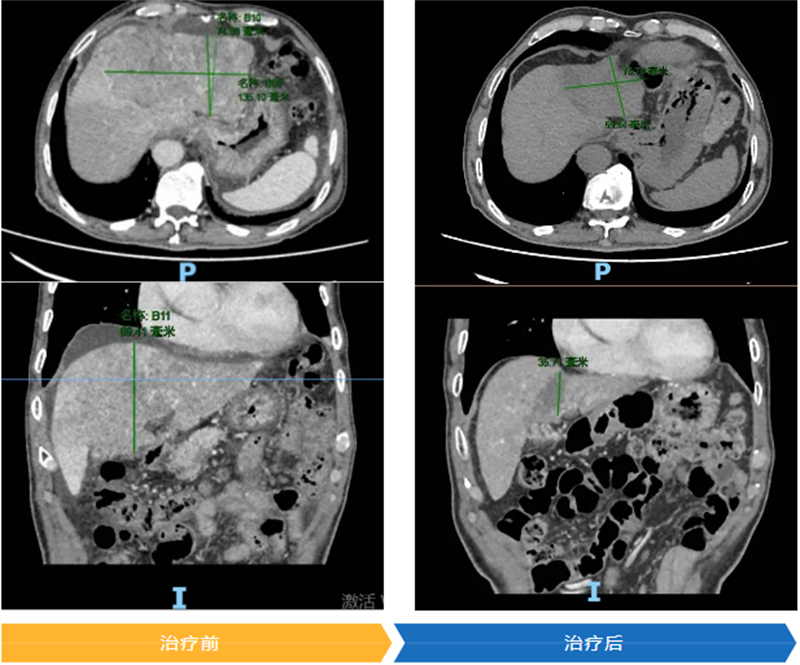

入院后,肝臟增強磁共振檢查結果令人揪心:原發性肝癌并肝內轉移灶,右心房、上腔靜脈、肝右靜脈、門靜脈主干等多處受累并癌栓形成。按照肝癌診療指南,此時肝癌已發生遠處轉移,而且右心房癌栓隨時可能脫落,引發肺動脈栓塞甚至猝死,情況危急。由于韋大叔已有遠處轉移,肝功能較差,存在手術和介入治療的禁忌癥,肝癌MDT團隊建議他進行免疫+靶向抗腫瘤治療。

幸運的是,在家人的堅持和悉心照料下,一個月后韋大叔返院復查時,肝腫瘤縮小,靜脈癌栓也有所消退,他自己也感覺身體輕松了許多。截至2025年3月,韋大叔的肝癌標志物基本降至正常,復查CT、磁共振顯示肝腫瘤活性降低,經過調整,肝功能損害也逐漸好轉,精神體力狀態良好,正在醫師指導下堅持治療和復查。這意味著韋大叔不僅有可能實現長時間帶瘤生存,甚至在醫院的肝癌全程管理方案治療下,還有望實現手術切除腫瘤。